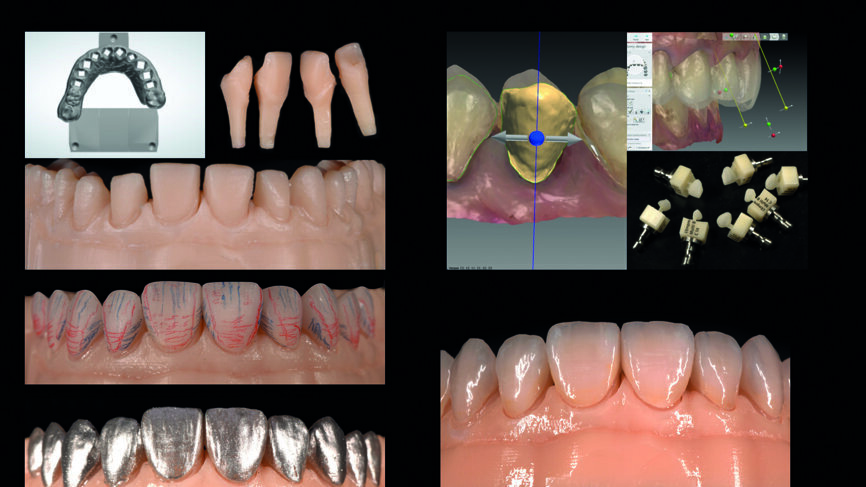

Fig. 13 : Flux de travail analogique (modèles positifs unitaires réfractaires, fabrication des facettes, ajustements, coloration/glaçage).

Fig. 14 : Flux de travail numérique (modèle imprimé en 3D, facettes réalisées en technique CFAO, ajustements, coloration/glaçage).

Une prothèse provisoire a été réalisée numériquement en Telio CAD (Ivoclar Vivadent) dans l‘unité d’usinage CNC select de Wieland Dental. La conception a été réalisée à l‘aide du logiciel DentalDesigner, version 2015, de 3Shape (Figs. 12a et b). Deux jeux de restaurations définitives ont été fabriqués.

Le jeu de facettes en céramique feldspathique a été fabriqué en IPS Style (Ivoclar Vivadent) sur un modèle en plâtre-pierre, tandis qu‘un bloc IPS Empress CAD Multi (Ivoclar Vivadent) a été utilisé pour le jeu numérique (Figs. 13 et 14). Les deux jeux ont été évalués en bouche avec une pâte d‘essai afin de comparer les propriétés optiques des facettes feldspathiques et des facettes réalisées en technique CFAO (Figs. 15a–c).

La prise d‘une empreinte intra-orale numérique est une autre procédure clinique qui s‘avère excellente par rapport à la technique d‘empreinte classique. Le plan de traitement numérique et le mock-up associé sont de puissants outils de communication à la disposition du chirurgien-dentiste, quoique l‘utilisation du logiciel exige des compétences particulières. Au regard du travail en laboratoire, mis à part les étapes de coloration et de glaçage, la plupart des techniques analogiques demandent plus de temps (fabrication des modèles positifs unitaires réfractaires, fabrication des facettes, ajustements) (Figs. 18a et b). Dans ce cas, le résultat esthétique des facettes en céramique feldspathique résultait d‘un choix subjectif mais le flux de travail analogique est beaucoup plus exigeant. Vu la réduction de la difficulté, de la vitesse, de la complexité et du désagrément causé au patient, l‘approche numérique est plutôt à privilégier (Figs. 18a et b).